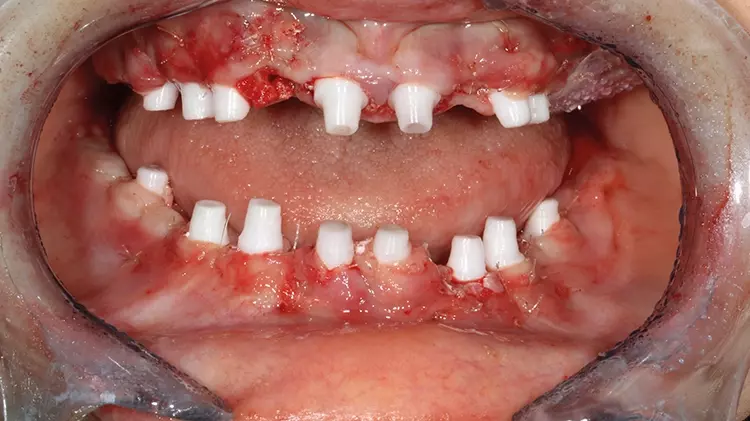

Abb. 15: Auch die UK-Implantate weisen trotz deutlicher Kieferkamm-Atrophie

und mit nur minimalinvasiven, einzeitigen Knochenaufbaumaßnahmen eine hohe

Primärstabilität auf. SDS

Abb. 15: Auch die UK-Implantate weisen trotz deutlicher Kieferkamm-Atrophie und mit nur minimalinvasiven, einzeitigen Knochenaufbaumaßnahmen eine hohe Primärstabilität auf.

Im Unterkiefer wurden nachfolgend nach gleicher Systematik erst die schienengeführte Spätimplantation vorgenommen, bevor die Sofortimplantationen im UKFZB folgten. Vereinzelte Knochenaufbaumaßnahmen erfolgten lediglich mit intraoralen Eigenknochen- sowie allogenen Spänen. In regio 33 erfolgte noch ein direkter Knochenaufbau mit einer aus regio 38 gewonnenen Knochenschale.

Um die Implantate wurden Eigenblutmembranen aus PRF (Platelet Rich Fibrin) eingelegt, um die Wundheilung zu fördern und zu beschleunigen [10-12]. Die Gingiva wurde anschließend atraumatisch um die Tissue-Level-Implantate mit den Knochenspänen und PRF-Matrices vernäht.